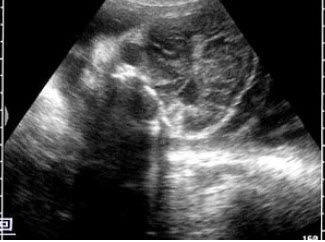

10、单项选择题

某患者右下腹痛,血尿,根据超声声像图,最可能的诊断为()

A.右肾结石

B.右输尿管下段结石

C.阑尾炎

D.膀胱结石

E.输尿管肿瘤